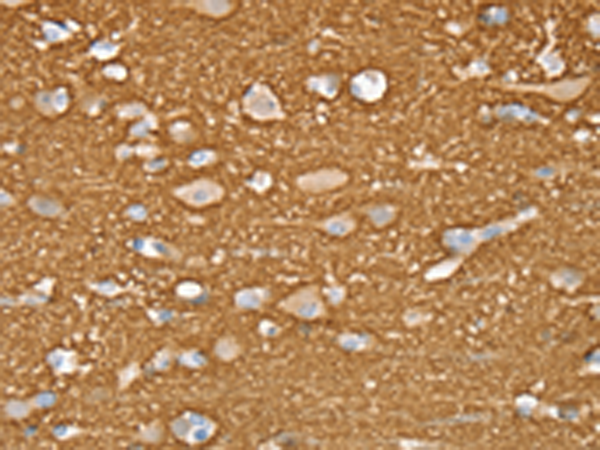

分类: 科研抗体货号: P08818别名: P67; NSEC1; UNC18; RBSEC1; MUNC18-1应用: WB,IHC反应种属: Human, Mouse, Rat